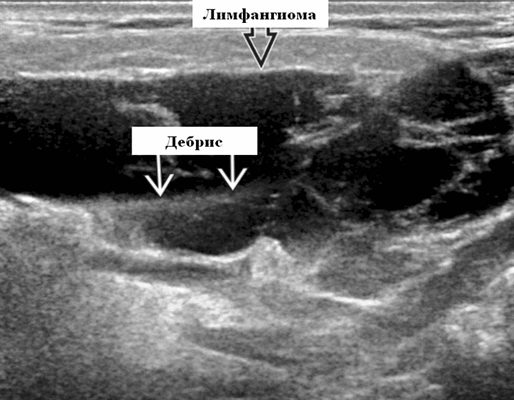

Околоушная лимфатическая мальформация

Синонимы. Пороки развития сосудов лимфатического типа. Спектр болезней. Венолимфатическая мальформация (ВЛМ): элементы венозной сосудистой мальформации (ВСМ) и ЛМ в одном и том же образовании. Лимфангиома и кистозная гигрома (старые термины)

Определение. Аномальное скопление расширенных лимфатических каналов, выстланных эндотелиальными клетками. Почти все они врожденные, возникшие в результате аномального развития лимфатической системы. Очень редко может быть вторичным по отношению к травме или операции.

Результаты ультразвукового исследования. Серошкальное УЗИ. Более крупные околоушные лимфангиомы могут быть обнаружены при пренатальном УЗИ. Чаще мультилокулярный, чем монокулярный. Кистозные пространства могут быть округлыми или вкраплениями. Поверхностные поражения сжимаются ультразвуковым датчиком. Внешний вид зависит от того, было ли ранее кровотечение / инфекция. Негеморрагический / неинфицированный лимфаангимоы выглядят на УЗИ как однокамерные или многокамерные (чаще) анэхогенные сжимаемые кисты с тонкими стенками и промежуточными септами. Несмотря на большие размеры, существенного масс эффекта нет. Тонкие незаметные стенки с задним акустическим усилением. Цветной допплер: в области поражения нет кровеносных сосудов. Геморрагический / инфицированный тип лимфатической мальформации. Однокамерные или многокамерные гетерогенные кисты с неровными стенками, внутренним дебрисом. Несжимаемые датчиком и гипоэхогенные полости с толстыми стенками и перегородками. Уровни жидкости-жидкости из-за осаждения и разделения жидкостей предполагают предшествующее кровотечение. Цветной допплер: при заражении; васкуляризация может быть видна в стенках, перегородках и прилегающих мягких тканях